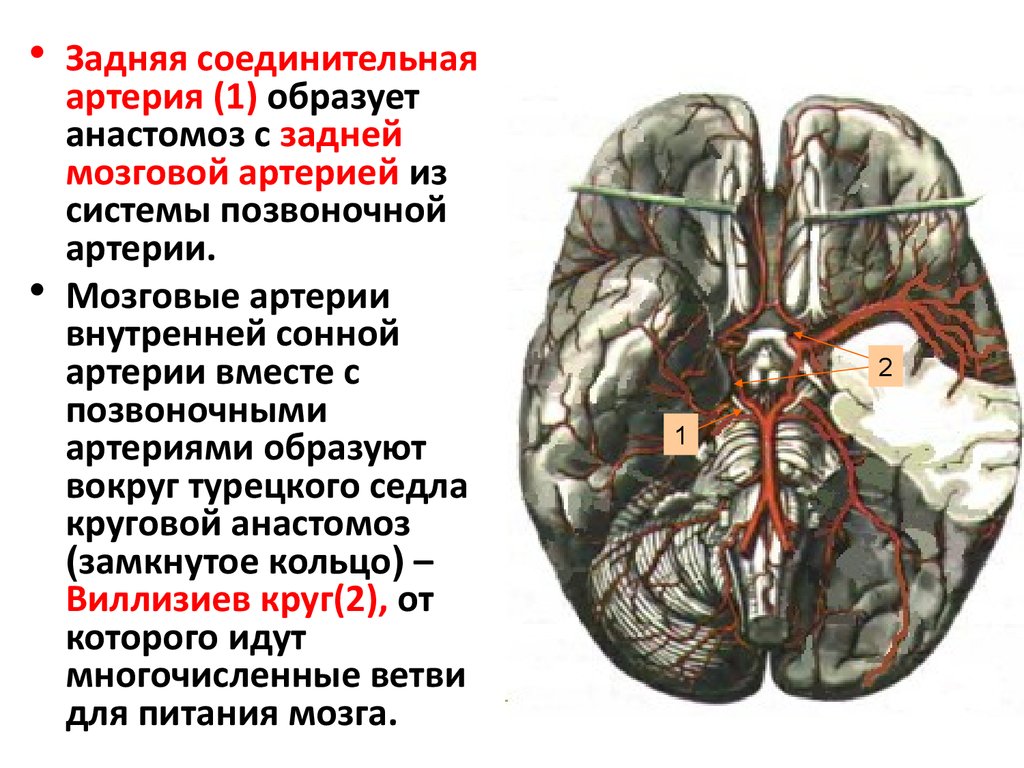

Анатомия: Задняя соединительная артерия мозга